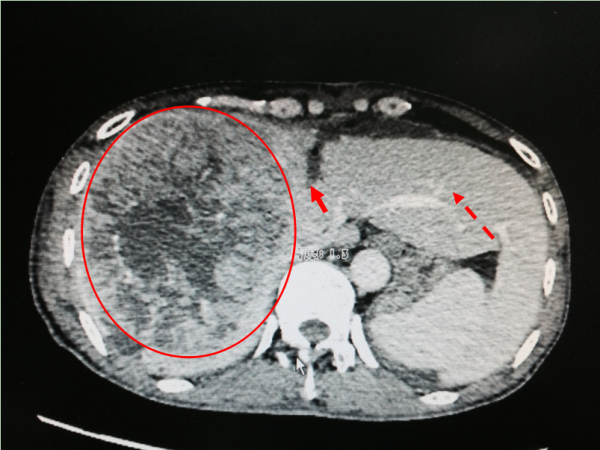

ALPPS第一步(门静脉结扎及左右半肝的离断)手术后CT图:红圈为肝肿瘤;实心箭头为左右半肝离断处;虚线箭头为增生左肝叶。